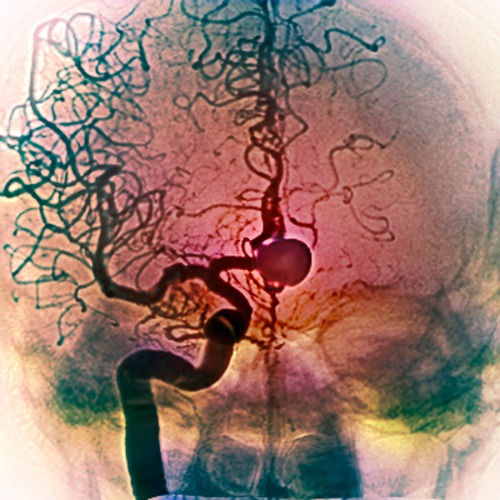

An intracranial aneurysm (round structure) is a section of an artery in the brain that starts to weaken and is at risk of bursting. © K H FUNG / SCIENCE PHOTO LIBRARY

Deadly danger lurks in the brain of one in 20 people. A section of an artery in the brain can start to weaken, ballooning into something called an intracranial aneurysm (IA) that is at risk of bursting.

Researchers found that 90% of the aneurysms (pictured) they tested had mutations in a common set of genes. © SOVEREIGN / ISM / SCIENCE PHOTO LIBRARY